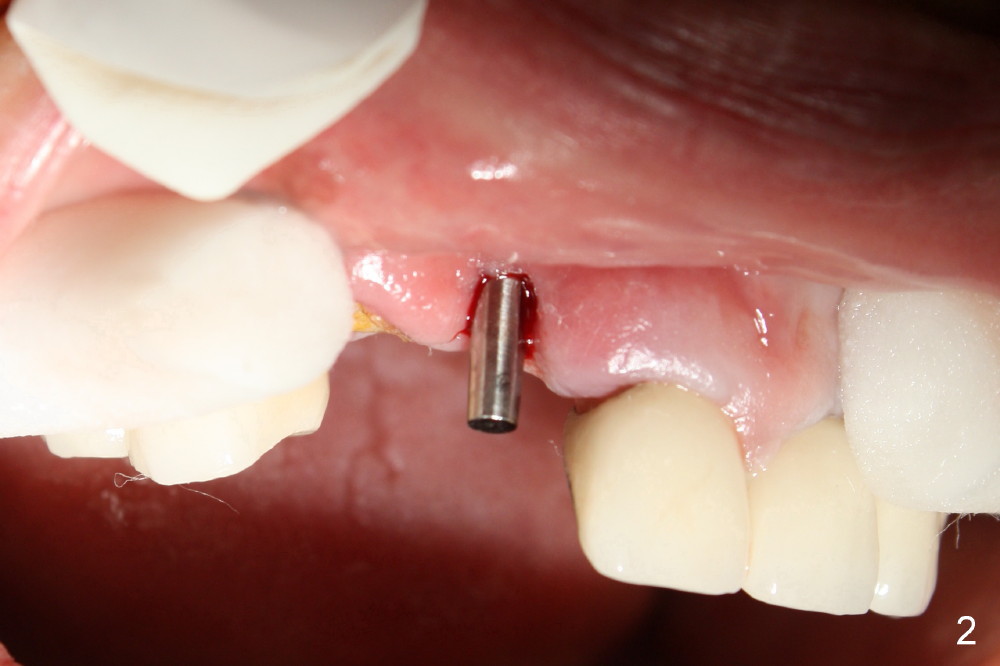

Finally the displaced implant is exfoliated itself, leaving a crater (Fig.1 arrowheads). CBCT shows the knife-edged ridge post exfoliation of the implant at the site of #7 (Fig.5, as compared to that prior to exfoliation). After using 1.5 mm pilot drill at 17 mm and 2.0 mm at 14 mm (Fig.5 insert), a 3.0x17 mm one piece angled (15 º) implant is placed (Fig.2, 10). Palatal view reveals that the implant is placed buccally (Fig.3); ideally the implant should be more palatal (Fig.3 insert: circle). Please take postop CBCT to confirm the placement. The buccal placement is partially related to the elongated tooth (Fig.4).

The reason that the implant is re-deviated buccally is that the coronal portion of the palatal plate is dense (Fig.6 *) and pushes the one piece implant buccally (Fig.7) while the latter is being inserted.